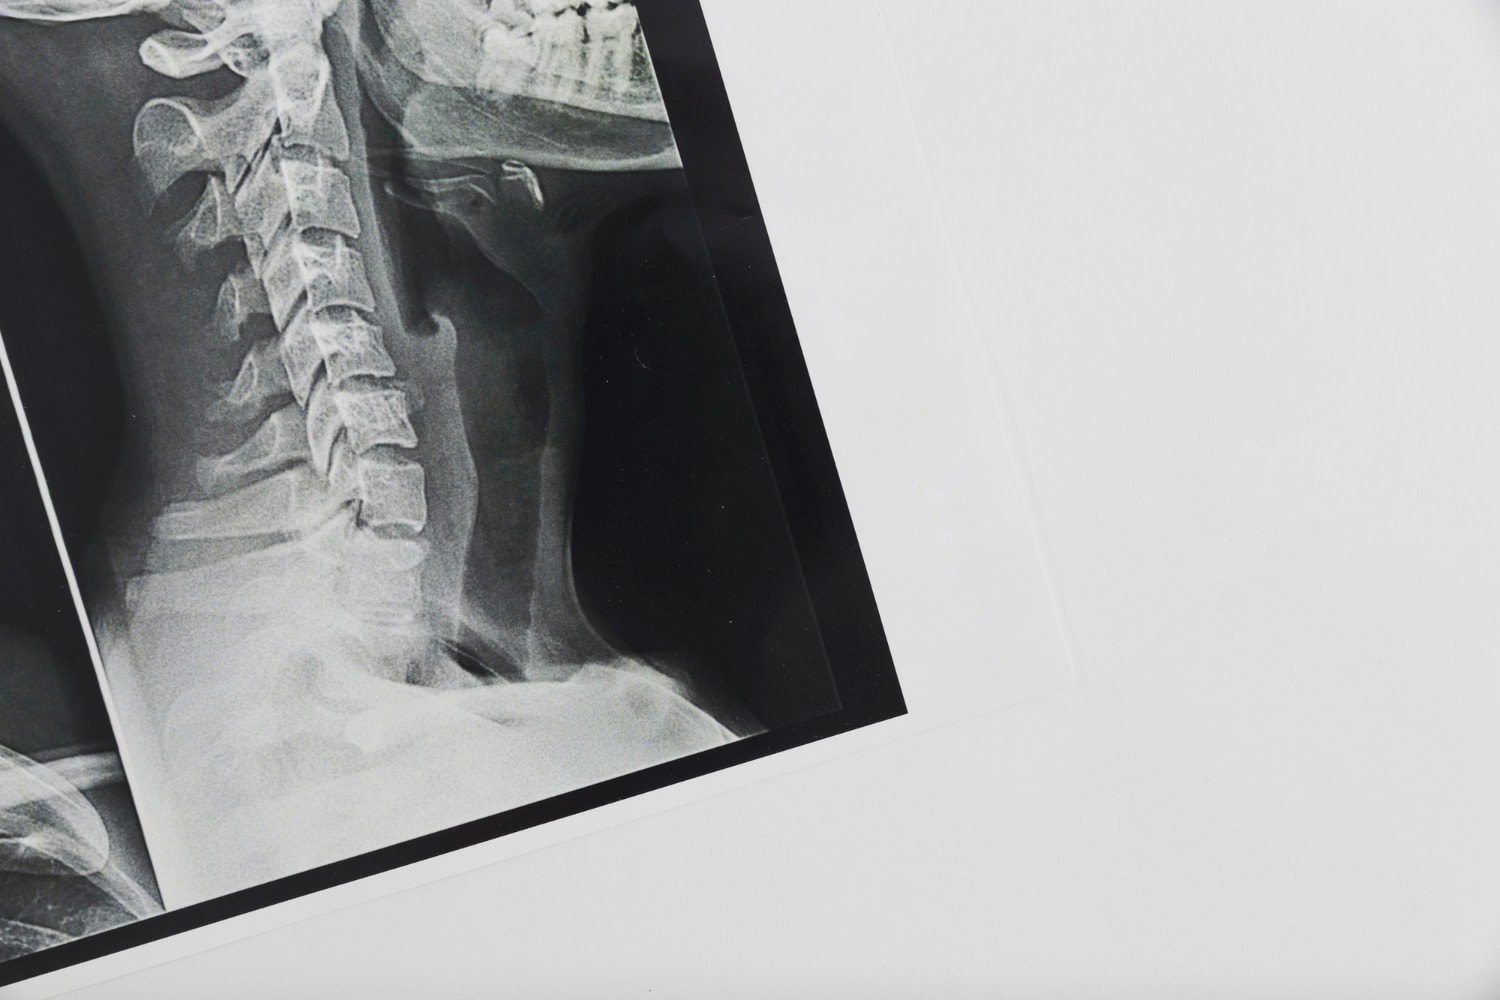

Chirurdzy z Centrum Medycznego Hadassah przeprowadzili skomplikowaną operację u 12-letniego chłopca, który doznał rzadkiego urazu znanego jako zwichnięcie kręgosłupa w odcinku szyjno-potylicznym. Znacznie częściej spotykana nazwa to wewnętrzna dekapitacja, gdyż w istocie tym właśnie jest – zerwaniem więzadeł stabilizujących między potylicą a pierwszym kręgiem kręgosłupa (tzw. dźwigaczem).

Okoliczności wypadku są tu nieistotne i trudno wyobrazić sobie, jak chłopiec musiał zostać niefortunnie uderzony, by doszło u niego do wewnętrznej dekapitacji. Pomoc na szczęście przyszła błyskawicznie i został przetransportowany drogą lotniczą na oddział urazowy szpitala Hadassah w En Kerem, gdzie stwierdzono poważne uszkodzenie więzadeł utrzymujących tylną podstawę jego czaszki, pozostawiając ją “odłączoną” od dźwigacza. Uraz ten jest bardzo rzadki u dorosłych, a tym bardziej u dzieci.